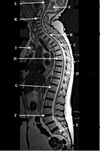

1

Q

What is letter A?

A

4TH VENTRICLE

What is letter B?

CEREBELLUM

3

What is letter C?

POSTERIOR ARCH OF C1

How well did you know this?

Not at all

2

4

5

Perfectly

What is letter D?

What is letter E?

CSF